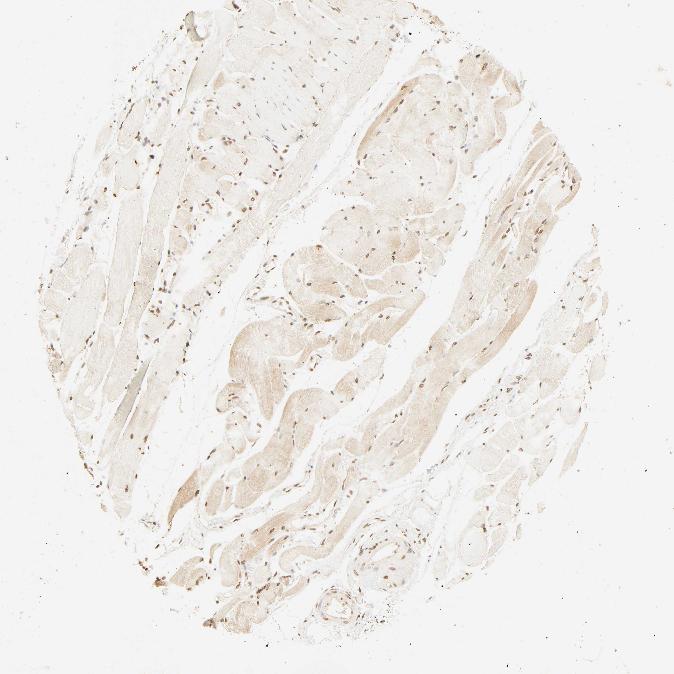

SKELETAL MUSCLE - Antibody stainingi

Antibody staining in the annotated cell types in the current human tissue is reported as not detected, low, medium, or high, based on conventional immunohistochemistry profiling in selected tissues. This score is based on the combination of the staining intensity and fraction of stained cells.

Each image is clickable and will lead to virtual microscopy that enables deeper exploration of all samples and also displays staining intensity scores, fraction scores and subcellular localization as well as patient and tissue information for each sample.

Antibody HPA041344Antibody HPA049132Antibody CAB000362Antibody CAB005419

Myocytes MediumHighLowMedium